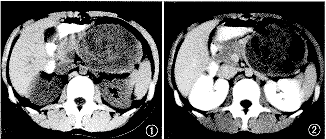

CT扫描:胰腺尾部可见一类圆形团块性病变,密度较低且不均匀,边缘清楚,大小约9.3 cm×7.6 cm(图1)。增强扫描肿瘤呈轻度不均匀强化,内见不规则坏死区,未见转移征象(图2)。

图1 CT平扫,示胰腺尾部巨大类圆形软组织包块,密度较低且不均匀,边缘清楚

图2CT增强扫描示肿瘤轻度强化,内见不规则坏死区,未见转移征像